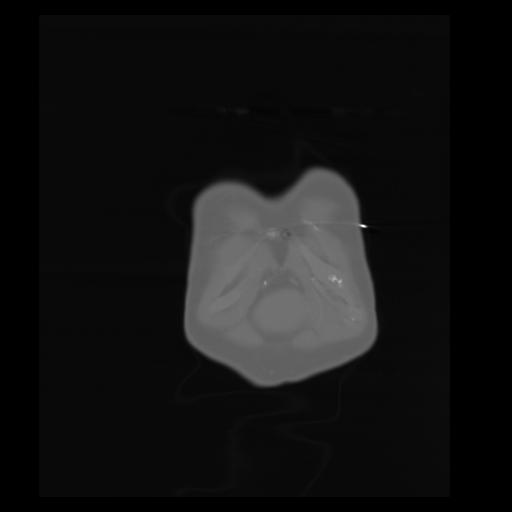

29 CUERPO,CE,Coronal,3.000,CUERPO,Coronal,